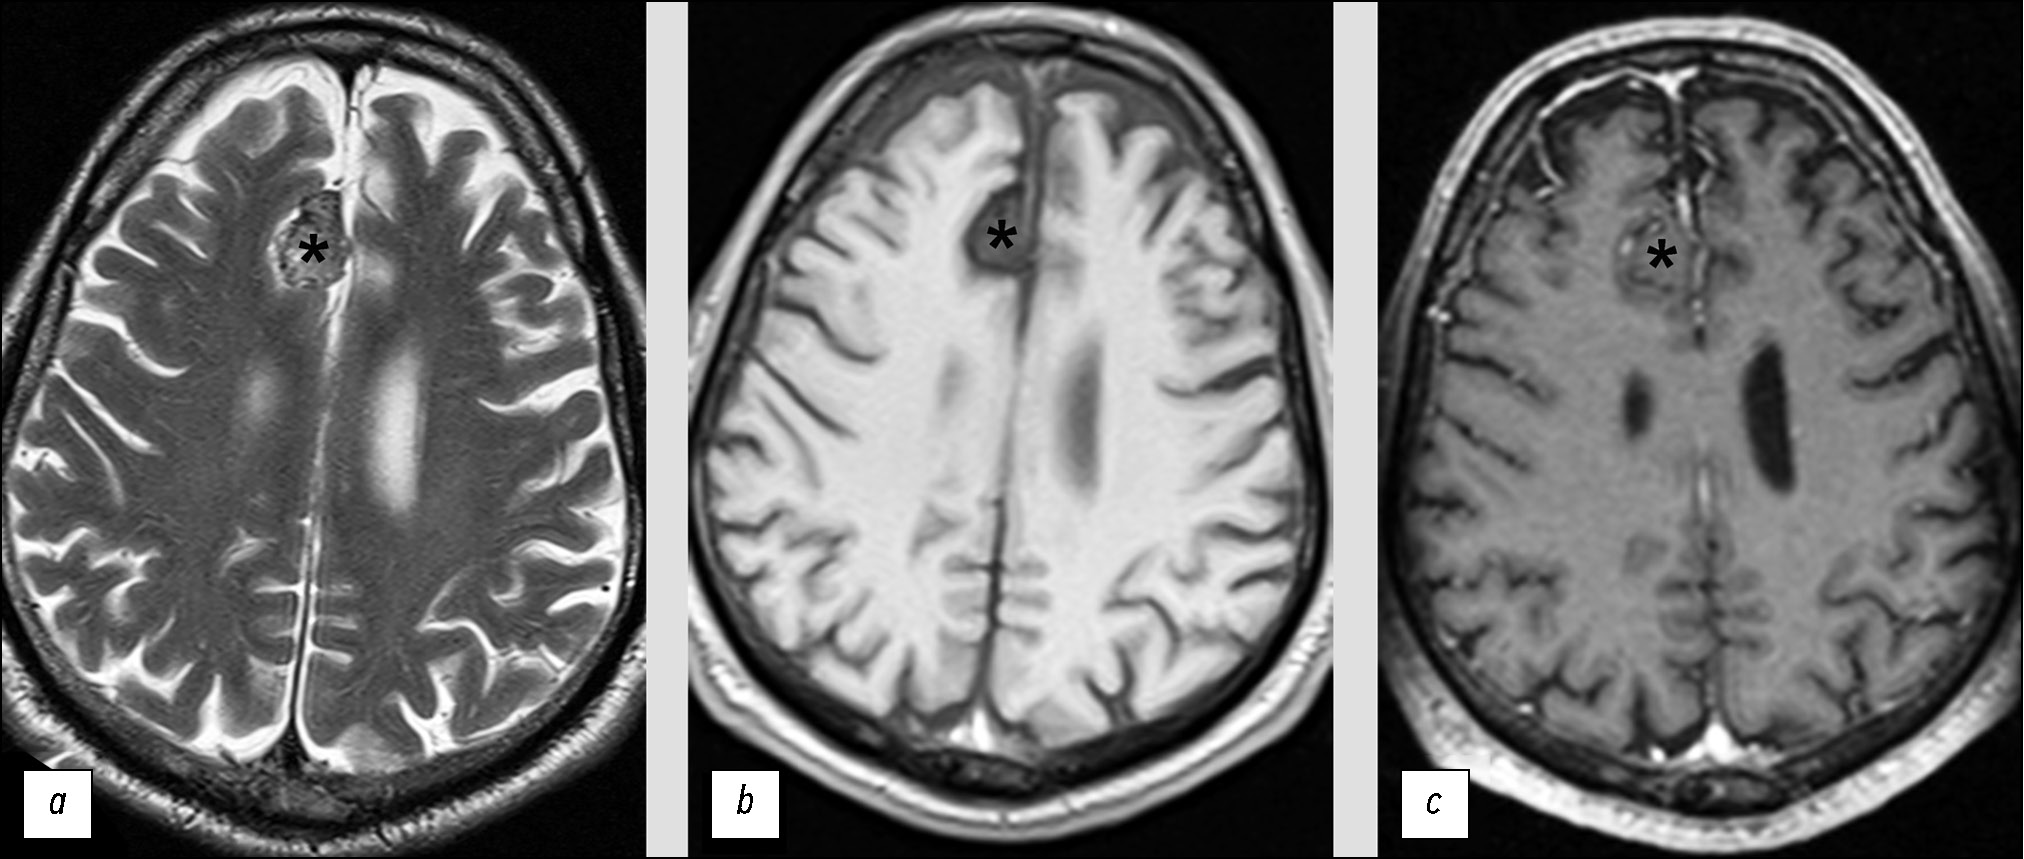

В двух следующих клинических примерах (рис. 7 и рис. 8) представлены МРТ-изображения пациентов с солитарными фиброзными опухолями. В обоих случаях опухоли на основании оценки МРТ были ошибочно определены как менингиомы. Вероятной причиной диагностических ошибок явилось сочетание двух факторов: редкость СФО и схожесть их МРТ-проявлений с менингиомами.

Рис. 7. Солитарная фиброзная опухоль, имеющая сходную МРТ-семиотику с доброкачественной менингиомой: a — Т2-ВИ; b — Т1-ВИ; c — Т1-CE.

В передних отделах межполушарной щели определяется внемозговое образование (*).

Рис. 8. Солитарная фиброзная опухоль, имеющая сходную семиотику магнитно-резонансной томографии со злокачественной менингиомой: a — Т2-ВИ; b —Т1-ВИ; c — Т1-CE.

Инструментальная диагностика. При выполнении МРТ данных за травматические изменения не выявлено, однако в передних отделах межполушарной щели определяется внемозговое образование, размерами 2,2×1,6×2,3 см (см. рис. 7). Опухоль широко прилежит к серпу большого мозга, чётко отграничена от вещества мозга, структура её достаточно однородная. После контрастирования отмечается невыраженное повышение МР-сигнала от ткани опухоли.

Дифференциальная диагностика. Выявленное образование было ошибочно классифицировано как типичная менингиома. Единственным признаком, позволяющим заподозрить иную опухоль, являлось невыраженное контрастирование, но данный симптом может наблюдаться и при менингиомах.

Лечение. Пациентке выполнена резекция опухоли, гистологическое заключение: гемангиоперицитома/солитарная фиброзная опухоль (Grade 1), С70.0 9150/01.

Инструментальная диагностика. При выполнении МРТ в левой лобной области было выявлено внемозговое образование, размерами до 6,0×4,0×6,3 см (см. рис. 8). Опухоль без чёткого отграничения от вещества мозга, с зоной отёка по периферии. Структура образования неоднородная, в том числе за счёт кровоизлияния. Контрастирование невыраженное и неоднородное.

Дифференциальная диагностика. На основании того, что образование имеет признаки, характерные для злокачественных менингиом, заключение рентгенолога было ошибочным. Выявленное образование отнесено к атипичным менингиомам.

Лечение. Пациенту выполнена резекция опухоли, гистологическое заключение: гемангиоперицитома/солитарная фиброзная опухоль (Grade 2), С70.0 9150/32.